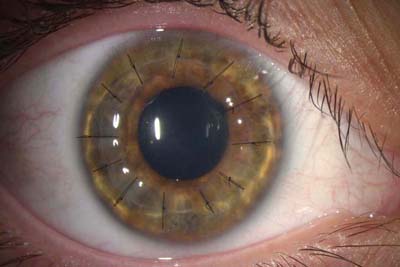

Queratoplastia de Espesor Total o Penetrante.

Se realiza cuando todas las capas de la córnea están comprometidas. El diámetro de los injertos oscila entre 7.0 y 9.0 mm según el área de compromiso corneal. Se sutura con puntos separados borde a borde o con sutura continua de poliamidas (Nylon). La cicatrización es lenta y los puntos se retiran entre los 6 y los 12 meses de post-operatorio.

Queratoplastia Penetrante